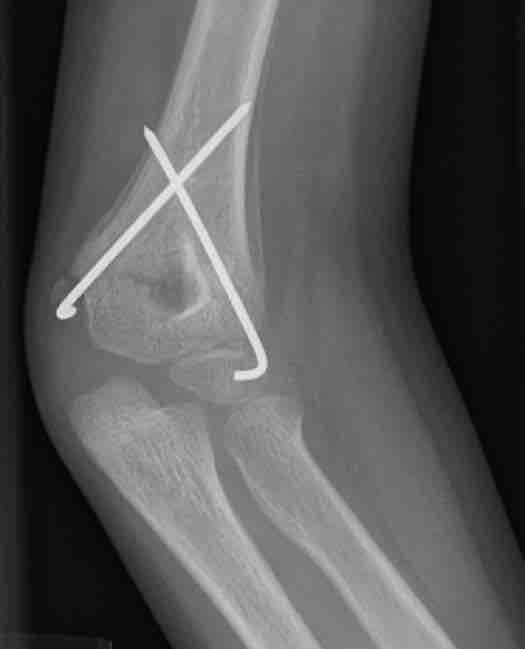

Healing fracture

This figure depicts a radiograph of a child's healing supracondylar humeral fracture that has been treated with closed reduction and pinning. This image, taken three weeks post injury, demonstrates the benign periosteal reaction of normal healing bone.

This is a radiographic image (x-ray) of a child's healing supracondylar humeral fracture that has been treated with closed reduction and pinning. This image, taken three weeks post injury, demonstrates the benign periosteal reaction of normal healing bone.